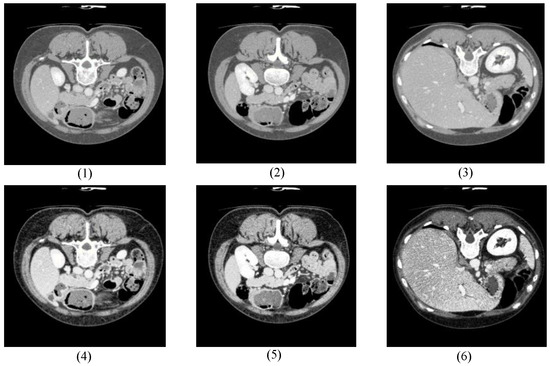

4.1.1. Dataset